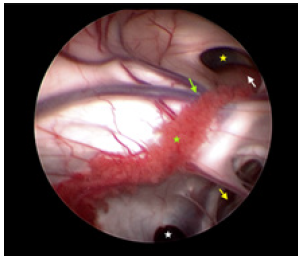

Because of the limited space on the right side, the entry point was chosen on the left frontal incision. After general endotracheal tube anesthesia, the patient was secured in supine position with head on a horse-shaped headrest. Endoscopic Third Ventriculostomy (ETV), Endoscopic Tumor Biopsy (ETB) and Ommaya reservoir insertion were performed successively through the left frontal burr hole (LOTTA Endoscope; Karl Storz, Tuttlingen, Germany) (Figure 3). A catheter was inserted at the opening of the cyst and an Ommaya reservoir was anchored subcutaneously beside the incision. The post-operative course was uneventful. The result of the histopathological examination was low-grade glioma (Figure 4).

Figure 3: Under the vision of neuroendoscopy, the dilated Moron hole (yellow star), the tumor (white arrow), the penetration of the Septum pellucidum (yellow arrow), the thalmostriate vein (green arrow), choroid plexus (yellow star) and the opening (white star) of the cyst of superior to cerebellums were confirmed.